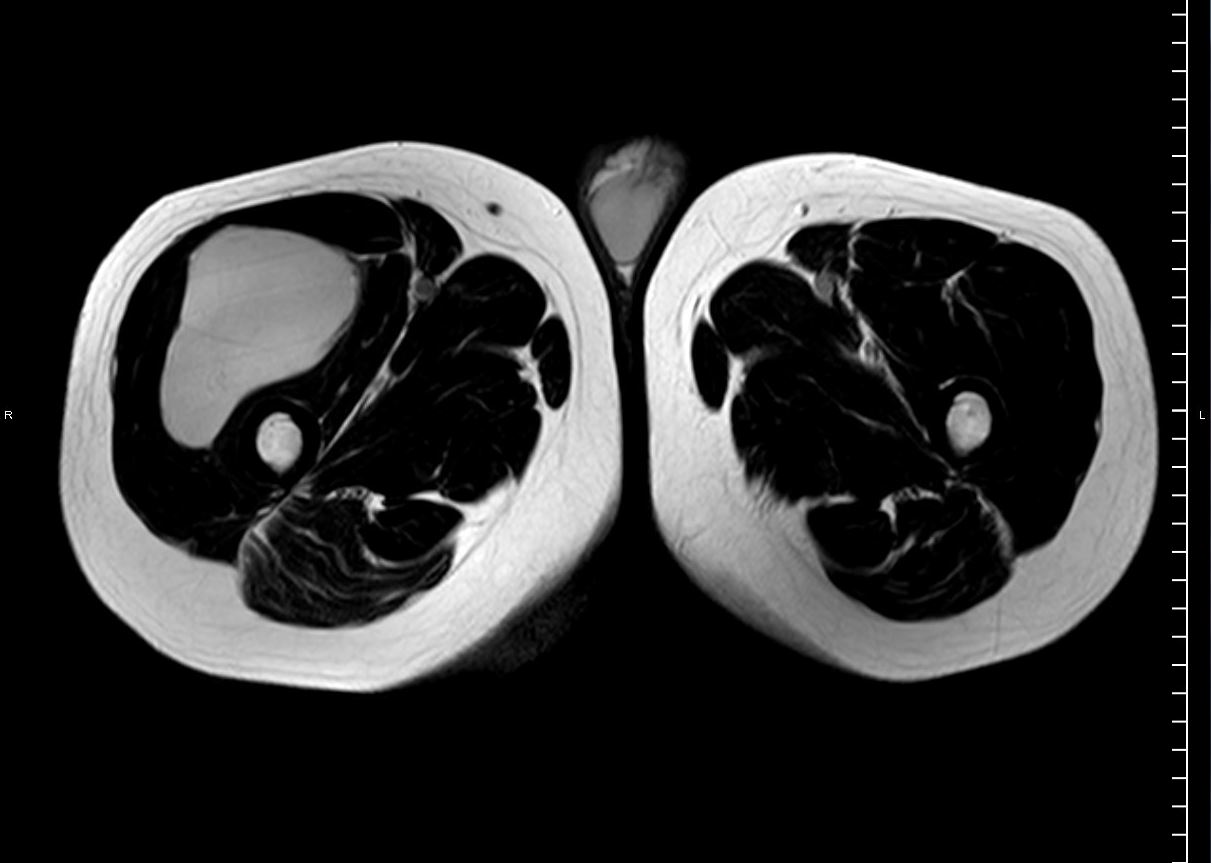

RM t2 axial

HALLAZGOS RADIOLÓGICOS